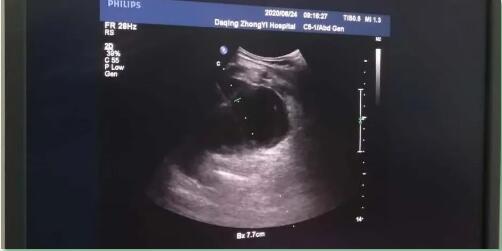

患者入院前三日突然出现右上腹部疼痛,发作时疼痛剧烈,无法忍受,伴有体温升高,巩膜黄染,肝功能异常等症状。入院后经查,诊断为重症胆囊炎,彩超显示:胆囊大小约为11.0*5.0cm,胆囊壁厚度为1.0cm成双边征。

在超声医学科主任赵春梅的全力配合下,使用彩色多普勒超声扫查,确定进针点、进针角度及进针深度,于井波主任进行操作。仅用10分钟就完成了胆囊穿刺引流术,整个过程非常顺利,患者全程没有感到任何不适,术后恢复良好。